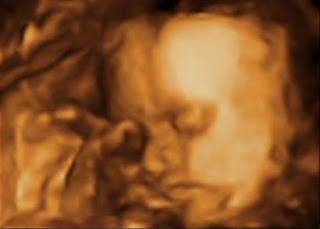

Meu papai, quando me viu assim, gordinha, chorou muito.

A mamãe chorou ontem à noite quando, lá na minha casa, eles se deitaram no sofá e ficaram me vendo na TV, e o papai ficou falando que eu sou a cara dela… Meus pais são muito fofos. Eles dão gritinhos e dizem: ohhhhhhhhh…. aiiiiiiiii…. óóóóólhaaaa. Eles são muito queridos, estão muito babões e cada vez mais unidos esperando por mim.

Ói eu aí!

Mas aí comecei a me soltar… Abri um bocão e falei alguma coisa, mas ninguém me ouviu. Tem muita água aqui, sacomé…